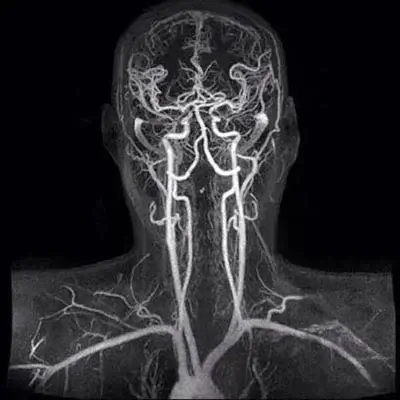

МРТ-діагностика судин додатково займе 15 хвилин. Але дозволить з’ясування наявності проблем з судинами. Тому, що потемніння в очах – це найчастіше судинна проблема.

Достатньо МРТ судин без контрасту. Завдання – прослідкувати хід судин і з’ясувати чи не має кровообіг мозку вроджених чи набутих дефектів.

МРТ судин і УЗД судин дають різні дані. МРТ судин – дозволяє бачити статичну картину судинного русла, що корисно для виявлення певних вроджених чи набутих дефектів. Наприклад – тромбозу чи недорозвиток судини. В свою чергу, УЗД висвітлює фізичні характеристики кровотоку в різних судинних басейнах, які можуть призводити до потемніння в очах та інших патологій головного мозку.